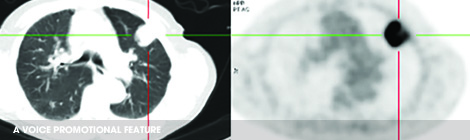

EARLY stage lung cancer patients unable to undergo surgery are eing offered a life-line with hi-tech radiation therapy. Stereotactic radiation treatment uses advanced imaging technology to deliver a high dose of radiation, very accurately and precisely to a tumour, sparing the surrounding sensitive organ. With conventional radiation therapy a patient would have to undergo 10…